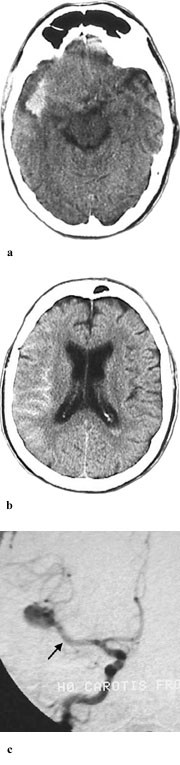

Spinalpunksjon var positiv for blod hos alle pasienter med negativ CT-funn (n = 6). Av disse var tre undersøkt på Advantage-maskinen og tre på Philips-maskinen. Hos en pasient var det angitt xantokromi (gul spinalvæske). CT-undersøkelse viste tegn på økt intrakranialt trykk hos en av disse pasientene. Cerebral angiografi viste intrakranialt aneurisme hos fire, men var normal hos to av disse pasientene. Det gikk lengre tid fra symptomdebut til CT-undersøkelse hos pasienter med negative CT-funn i forhold til dem med positive CT-funn (median 87 timer mot 3 timer og 55 minutter, p< 0,001).

En negativ CT-undersøkelse bør følges av spinalpunksjon dersom det er klinisk mistanke om blødning, spesielt dersom det er gått lang tid (>20 – 30 timer) fra symptomdebut til CT-undersøkelse. Det bør gå minst seks, helst 12 timer etter symptomdebut før spinalpunksjon utføres (1). Etter noen få dager faller sensitiviteten av CT-undersøkelse for påvisning av blod i subaraknoidalrommet markert (9). Dette skyldes at blodet etter en stund fordeler seg og resorberes fra subaraknoidalrommet. Blod i basale cisterner resorberes først, mens mengden blod over hemisfærene kan øke etter noen få dager, da cerebrospinalvæsken strømmer fra basis opp over hjernens konveksiteter (13). Studier viser at blod i subaraknoidalrommet som regel fjernes etter 6 – 10 dager, mens det kan gå 15 – 30 dager før intracerebrale hematomer får markert redusert attenuasjon (8).